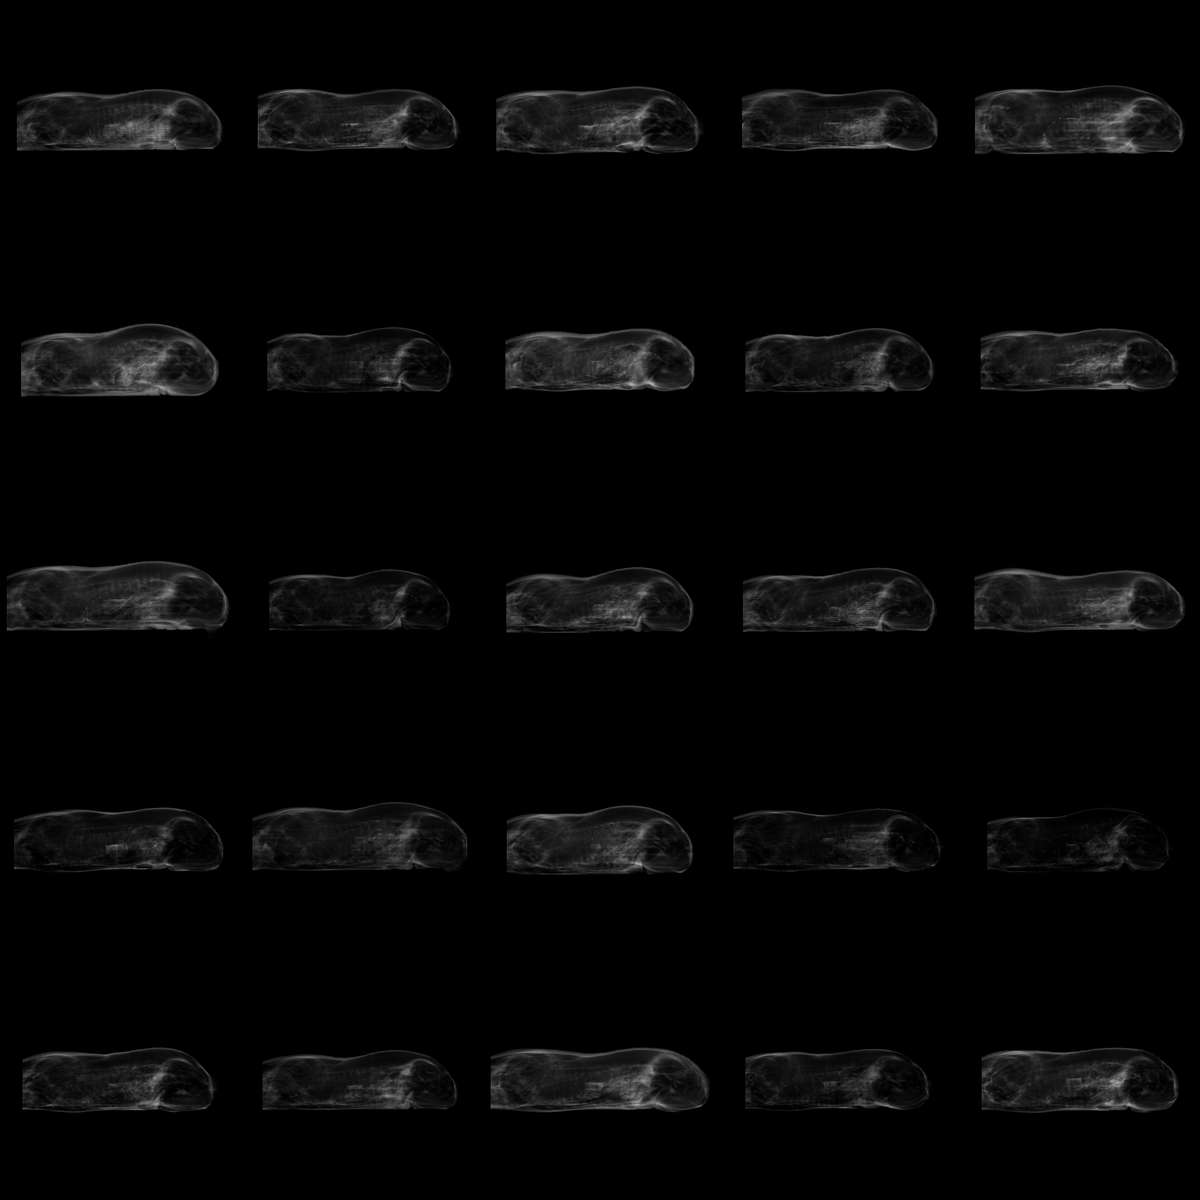

For swine, AIPheno detected 5,880 IVPs per image. These image variations, which encompass not only changes in fat content and distribution but also alterations in body length and body shape (Fig.S9C), were significantly associated with three loci. In contrast, four HDPs (total fat content, average fat content, and image-based body length and body height) were extracted for comparison, none of which yielded significant associations. The results showed that HDPs failed to capture the image variation of fat distribution, while the IVPs detected by AIPheno were able to successfully uncover the genetic basis behind swine fat distribution (Fig.2G).

Fig.2 AIPheno enhances the power of genetic discovery with scalable digitial phenotypes across multi-species datasets. A, Heritability distribution of the 420 image-variation phenotypes of human retinal fundus images detected by AIPheno (mean == 0.08, SD == 0.05, min == 0.009, max == 0.221). B, GWAS Manhattan plot for the Human Retinal Fundus dataset (p values were truncated at 1×101001\times 10^{-100}). In this plot, the p value for each SNP was the minimum p value of that SNP across all image-variation phenotypes GWAS results. The significance threshold was adjusted using a Bonferroni correction for the number of image-variation phenotypes (poriginal=5×108p_{\text{original}}=5\times 10^{-8}, pcorrection=1.19×1010p_{\text{correction}}=1.19\times 10^{-10}). The density plot below indicated the number of image-variation phenotypes with significant signals per 2 MB interval. Information for all lead SNPs, genetic loci, and candidate genes is provided in Table S1. C, Word cloud of reported phenotypes from the GWAS Catalog associated with the identified candidate genes. The word cloud results indicate that the most frequent word is Color, followed by terms associated with eye diseases ("Myopia," "Refraction," and "Error"), and then by tissues related to the eye or pigmentation ("Retinal," "Hair," "Eye," and "Macular"). D, Comparison of genetic discovery power between AIPheno and human-defined methods in Homo sapiens (human). For AIPheno, a large number of image-variation phenotypes were detected, such as pigmentation, retinal lesions, and the morphology of the optic disc and vasculature (Also see dynamic videos included in the Data S4-S8). For human-defined phenotypes, Fractal Dimension quantifies vascular branching complexity, Vascular Density is defined as the total number of segmented pixels given a consistent field of view and fixed pixel dimensions across all individuals, and Color Channels refer to the mean values of the R, G, and B image channels. Left bar: Percentage of lead SNPs reported by the comparison methods overlapping with AIPheno loci. Bottom right bar: Percentage of AIPheno loci that overlapped with reported lead SNPs. Top right bar: Percentage of AIPheno-specific loci. E, Comparison of genetic discovery power between AIPheno and human-defined methods in Columba livia (domestic pigeon). GWAS results for all image-variation phenotypes of AIPheno with significant signals were aggregated to plot the Manhattan plot. The green dashed line highlights significant signals associated with the two types of phenotypes. The human-defined phenotypes are the "pearl" and "gravel" iris categories. The significance threshold of human-defined methods was 4.13×1094.13\times 10^{-9}. The significance threshold of AIPheno was adjusted using a Bonferroni correction for the number of image-variation phenotypes (poriginal=4.13×109p_{\text{original}}=4.13\times 10^{-9}, pcorrection=2.95×1011p_{\text{correction}}=2.95\times 10^{-11}). F, Comparison of genetic discovery power between AIPheno and human-defined methods in Oryza sativa (rice). The GWAS results with significant signals for image-variation phenotypes of AIPheno and human-defined phenotypes were aggregated separately to plot the Manhattan plots. The green dashed line highlights significant signals associated with the two types of phenotypes. The dashed line indicates the original significance threshold (poriginal=1.16×108p_{\text{original}}=1.16\times 10^{-8}). The effective thresholds were then determined by Bonferroni correction (dividing the original threshold by the number of phenotypes), resulting in pcorrection=1.05×109p_{\text{correction}}=1.05\times 10^{-9} for human-defined methods and pcorrection=2.75×1011p_{\text{correction}}=2.75\times 10^{-11} for AIPheno. The human-defined phenotypes are histogram-based mean, histogram-based variance, total projected area, height of the bounding rectangle, width of the bounding rectangle, ratio of total projected area to circumscribed box area, circumscribed box area, ratio of total projected area to hull area, ratio of perimeter to total projected area, perimeter, and green projected area. Information for all lead SNPs, genetic loci, and candidate genes of T13, identified using image-variation phenotypes, is provided in Table S2 to Table LABEL:table_s25. G, Comparison of genetic discovery power between AIPheno and human-defined methods in Sus scrofa (swine). GWAS results for all human-defined phenotypes were aggregated to plot the Manhattan plot. GWAS results for all image-variation phenotypes of AIPheno with significant signals were aggregated to plot the Manhattan plot. The green dashed line highlights significant signals associated with the two types of phenotypes. In the Manhattan plot, the dashed threshold line was set at poriginal=2.81×109p_{\text{original}}=2.81\times 10^{-9}, with pcorrection=7.02×1010p_{\text{correction}}=7.02\times 10^{-10} for human-defined methods and pcorrection=4.77×1013p_{\text{correction}}=4.77\times 10^{-13} for AIPheno. The human-defined phenotypes are total fat content, average fat content, and image-based body length and body height. Table S26 presents information on all lead SNPs, genetic loci, and candidate genes identified using image-variation phenotypes.

For swine, a peak identified by AIPheno was associated significantly with IVP(𝐯112,4)(\mathbf{v}_{112},4) (Fig.3F). Two candidate genes were identified via positional mapping and literature review: FABP3 and BMP2. In swine, genetic variants of FABP3 were associated not only with backfat thickness, but also with intramuscular fat content[54, 55]. Multiple studies have shown that BMP2 was associated with body shape, body size, and carcass morphology. Fan et al. reported that BMP2 was associated with increased body length, decreased body depth, and reduced body width[56]. BMP2 was reported by Li et al. to be associated with carcass straight length[57]. Similar observations were made by Zhang et al., who identified associations between BMP2 and carcass length, body length, body height, and BMIBL\text{BMI}_{\text{BL}} traits, which suggested that BMP2 was a strong candidate gene for body size due to its involvement in growth and bone development[58]. The interpretability results of AIPheno demonstrated consistency with previous studies, indicating changes in fat deposition and body length in swine. Interestingly, we discovered a variation in body shape not reported in previous research: the loin of the swine gradually became concave, which made the body shape progressively more slender. As shown in the std image, the image variation was diffused across the entire body region of the swine and is focused on the front and loin areas (Fig.3F). This visual discovery aligns remarkably with established findings, which identified BMP2 as a key candidate gene regulating Loin Muscle Depth (LMD)[59]. The depth of the loin muscle directly determines the contour of the pig’s back and loin; therefore, when a genetic variant of BMP2 leads to a shallower muscle, the external morphology naturally presents as a "concave" appearance. Thus, the visualization from AIPheno provides an actionable morphological meaning to these previously established quantitative traits.

Fig.3 AIPheno’s actionable interpretability validates and refines insights into established gene-phenotype associations. Identified genes for which AIPheno validated or refined established gene-phenotype associations are highlighted in blue. In std images, which are visualizations of the standard deviation for each pixel across the generated images, a brighter pixel indicates greater change at that point during image traversal. A, Interpretability analysis of IVP(𝐯1,11)(\mathbf{v}_{1},11) in domestic pigeon. The significance threshold was adjusted using a Bonferroni correction for the number of image-variation phenotypes (poriginal=4.13×109p_{\text{original}}=4.13\times 10^{-9}, pcorrection=2.95×1011p_{\text{correction}}=2.95\times 10^{-11}). A transition from the Pearl-type to the Gravel-type was observed; the white texture in the iris diminished gradually. As shown in the std image, image variation was focused on the region outside the pupil and light spot. Also see a dynamic video included in the Data S9. B, Interpretability analysis of IVP(𝐯1,1)(\mathbf{v}_{1},1) in rice. The significance threshold was adjusted using a Bonferroni correction for the number of image-variation phenotypes (poriginal=1.16×108p_{\text{original}}=1.16\times 10^{-8}, pcorrection=2.75×1011p_{\text{correction}}=2.75\times 10^{-11}). The plant height of rice decreased gradually. As shown in the std image, image variation was concentrated at the top and bottom of the plant. Also see a dynamic video included in the Data S10. C, Interpretability analysis of IVP(𝐯23,13)(\mathbf{v}_{23},13) in human. The significance threshold was adjusted using a Bonferroni correction for the number of image-variation phenotypes (poriginal=5×108p_{\text{original}}=5\times 10^{-8}, pcorrection=1.19×1010p_{\text{correction}}=1.19\times 10^{-10}, p values were truncated at 1×101001\times 10^{-100}). As the color gradually lightened, the visibility of the optic disc and vasculature progressively increased, in turn revealing greater complexity and width within the vasculature. As shown in the std image, image variation was not only diffused across the entire fundus region, but it was also concentrated in the optic disc and vascular areas. Also see a dynamic video included in the Data S11. D, Interpretability analysis of IVP(𝐯21,9)(\mathbf{v}_{21},9) in human. The significance threshold was adjusted using a Bonferroni correction for the number of image-variation phenotypes (poriginal=5×108p_{\text{original}}=5\times 10^{-8}, pcorrection=1.19×1010p_{\text{correction}}=1.19\times 10^{-10}). Pigmentary changes occurred, a tessellated fundus gradually developed, peripapillary atrophy appeared, and the retinal vessels progressively coarsened. The std image also showed that the image variation was distributed across the entire fundus, particularly concentrating on several areas: the tessellated lesions in the periphery and center, peripapillary lesions, and the vasculature. Also see a dynamic video included in the Data S12. E, Interpretability analysis of IVP(𝐯28,7)(\mathbf{v}_{28},7) in human. The significance threshold was adjusted using a Bonferroni correction for the number of image-variation phenotypes (poriginal=5×108p_{\text{original}}=5\times 10^{-8}, pcorrection=1.19×1010p_{\text{correction}}=1.19\times 10^{-10}). The severity of the tessellated fundus gradually decreased. The std image also revealed that these lesions were primarily concentrated in the fundus periphery, near the optic disc margin and the macula. Also see a dynamic video included in the Data S13. F, Interpretability analysis of IVP(𝐯112,4)(\mathbf{v}_{112},4) in swine. The significance threshold was adjusted using a Bonferroni correction for the number of image-variation phenotypes (poriginal=2.81×109p_{\text{original}}=2.81\times 10^{-9}, pcorrection=4.77×1013p_{\text{correction}}=4.77\times 10^{-13}). The body shape became progressively more slender with increased body length and a more concave loin, while fat deposition progressively increased. As shown in the std image, the image variation was diffused across the entire body region of the pig and was focused on the front and loin areas. Also see a dynamic video included in the Data S14.

In swine, AIPheno identified a peak on Chromosome 1, which was associated significantly with IVP(𝐯174,10)(\mathbf{v}_{174},10) (Fig.4D). Through the interpretability analysis, the porcine body parts in the image became increasingly brighter overall, which indicated an increase in the degree of whole-body fat deposition (Fig.4D). This increase was particularly evident in the backfat and abdominal regions in std image. Based on these image variations, and through positional mapping within the significant locus, two plausible functional candidate genes, SOD2 and IGF2R, were identified. In swine, no association between SOD2 and fat deposition has been reported in previous research. Post-developmental deletion of skeletal muscle-specific SOD2 induced systemic physiological effects through escalating mitochondrial deficits and subsequent impairment of energy metabolism in murine models. Additionally, SOD2 has been implicated in the modulation of lipid pathways, which demonstrated its direct association with both energy homeostasis and lipid metabolic regulation[81]. In humans, genetic variants of SOD2 were related to glucose metabolism[82]. More direct evidence has been demonstrated that genetic polymorphisms in SOD2 were associated with increased percentage of body fat and accumulation of visceral fat in obese populations, a finding that is directly aligned with our interpretability analysis[83]. For IGF2R, studies have also reported that its function is related to fat deposition. The IGF2 locus was associated with muscle mass and fat deposition in swine[84], and its receptor, IGF2R, may also be implicated in the variation of these traits. The exonic polymorphism of IGF2R was associated with obesity in humans[85]. Based on interpretability analysis and cross-species evidence, we propose that the SOD2-IGF2R locus is associated with whole-body fat deposition in swine.

Fig.4 AIPheno’s actionable interpretability uncovers biological insights into newly identified genes. A, Schematic diagram of domestic pigeon eye and iris anatomy. The different eye colors of the domestic pigeon are determined by the iris, which is composed of three layers. The outermost Anterior Border Layer and the middle Stroma contain pigment cells, within which yellow pteridines and reflective purines are found. The innermost Pigment Epithelium is rich in melanin. B, Manhattan plot and LD analysis of GWAS results. Results for all image-variation phenotypes were integrated for plotting, with two threshold lines indicating the significance levels before (p=4.13×109p=4.13\times 10^{-9}) and after (p=2.95×1011p=2.95\times 10^{-11}) Bonferroni correction that was based on the number of image-variation phenotypes. Newly identified genes are highlighted in pink. LD analysis was performed within a 300 kb region surrounding the lead SNP on chromosome 1. Significant signals clustered between the TMTC3 and KITLG genes. C, Interpretability analysis of IVP(𝐯3,10)(\mathbf{v}_{3},10) in domestic pigeon. The accumulation level of melanin was reduced gradually. The significance threshold was adjusted using a Bonferroni correction for the number of image-variation phenotypes (poriginal=4.13×109p_{\text{original}}=4.13\times 10^{-9}, pcorrection=2.95×1011p_{\text{correction}}=2.95\times 10^{-11}). The std image showed that variation in melanin levels was present throughout the iris, except for the pupil and the light spot. Also see a dynamic video included in the Data S15. D, Interpretability analysis of IVP(𝐯174,10)(\mathbf{v}_{174},10) in swine. The significance threshold was adjusted using a Bonferroni correction for the number of image-variation phenotypes (poriginal=2.81×109p_{\text{original}}=2.81\times 10^{-9}, pcorrection=4.77×1013p_{\text{correction}}=4.77\times 10^{-13}). Whole-body fat deposition increased, especially in the backfat and abdominal regions. The std image also showed that image variation was primarily concentrated in the backfat and abdominal regions. Also see a dynamic video included in the Data S16. E, Interpretability analysis of IVP(𝐯22,0)(\mathbf{v}_{22},0) in human. The significance threshold was adjusted using a Bonferroni correction for the number of image-variation phenotypes (poriginal=5×108p_{\text{original}}=5\times 10^{-8}, pcorrection=1.19×1010p_{\text{correction}}=1.19\times 10^{-10}). The optic disc (blue arrow) gradually moved downward with the fovea (red arrow) position unchanged, decreasing the disc-fovea angle (angle between the optic disc center and the foveola), while its size was reduced gradually. Such variations have been reported to be associated with ocular diseases. The std image showed that image variation was primarily concentrated in the optic disc and the connecting vasculature, while the fovea region showed almost no variation. Also see a dynamic video included in the Data S17. F, A single lead SNP can be statistically significant for multiple image-variation phenotypes. To resolve this, we first conducted a systematic min-p analysis to assign each lead SNP to the single image-variation phenotype with which it had the strongest association (smallest p value). Next, we constructed a Sankey diagram to visualize these relationships. Finally, to highlight novel discoveries, we selected associations involving lead SNPs that had no previously reported links to pigmentation or eye-related traits in the GWAS Catalog. In the diagram, chromosomes (left column) are linked to lead SNPs (center column) and their corresponding smallest p value image-variation phenotypes (right column). The lead SNPs in the central column are colored red if unreported previously in an eye or pigmentation context and blue if reported. The thickness of the lines connecting the columns is proportional to the log10(p)-\log_{10}(p) value of the lead SNP.